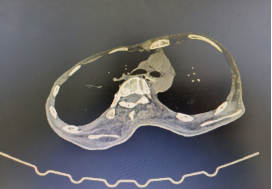

食管CT提示异物处于食管主动脉弓水平、食管第二狭窄处

患者因患有渐冻症十余年,胸廓及脊柱严重畸形、四肢肌肉萎缩、关节僵硬失去活动能力、且严重营养不良。2月22日,患者因进食时不慎将整块香肠吞下,出现胸骨后梗阻疼痛不适,大量喝水、吞咽干饭团均无法缓解症状,经UG环球国际附属第二医院食管CT检查有食管内异物,为食管内异物嵌顿,如不处理存在极大风险,最佳办法是全麻胃镜下取物。但患者身体特殊,无法满足麻醉要求,只能在普通胃镜下进行。在与患者本人及家属沟通后,接诊的张又莉医生与内二科主任徐魁、消化内镜中心主任高新生等科室医护专家团队讨论制定操作方案,于第二天进行异物取出。手术团队克服患者不能正常侧卧、没有麻醉等特殊状况下完成手术。术中患者心率一度升至170次/分,手术医生张又莉沉着冷静,5分钟顺利取出异物,术后进行完整胃镜检查提示异物取出干净,无残留,食管仅少许糜烂,患者当天顺利出院。